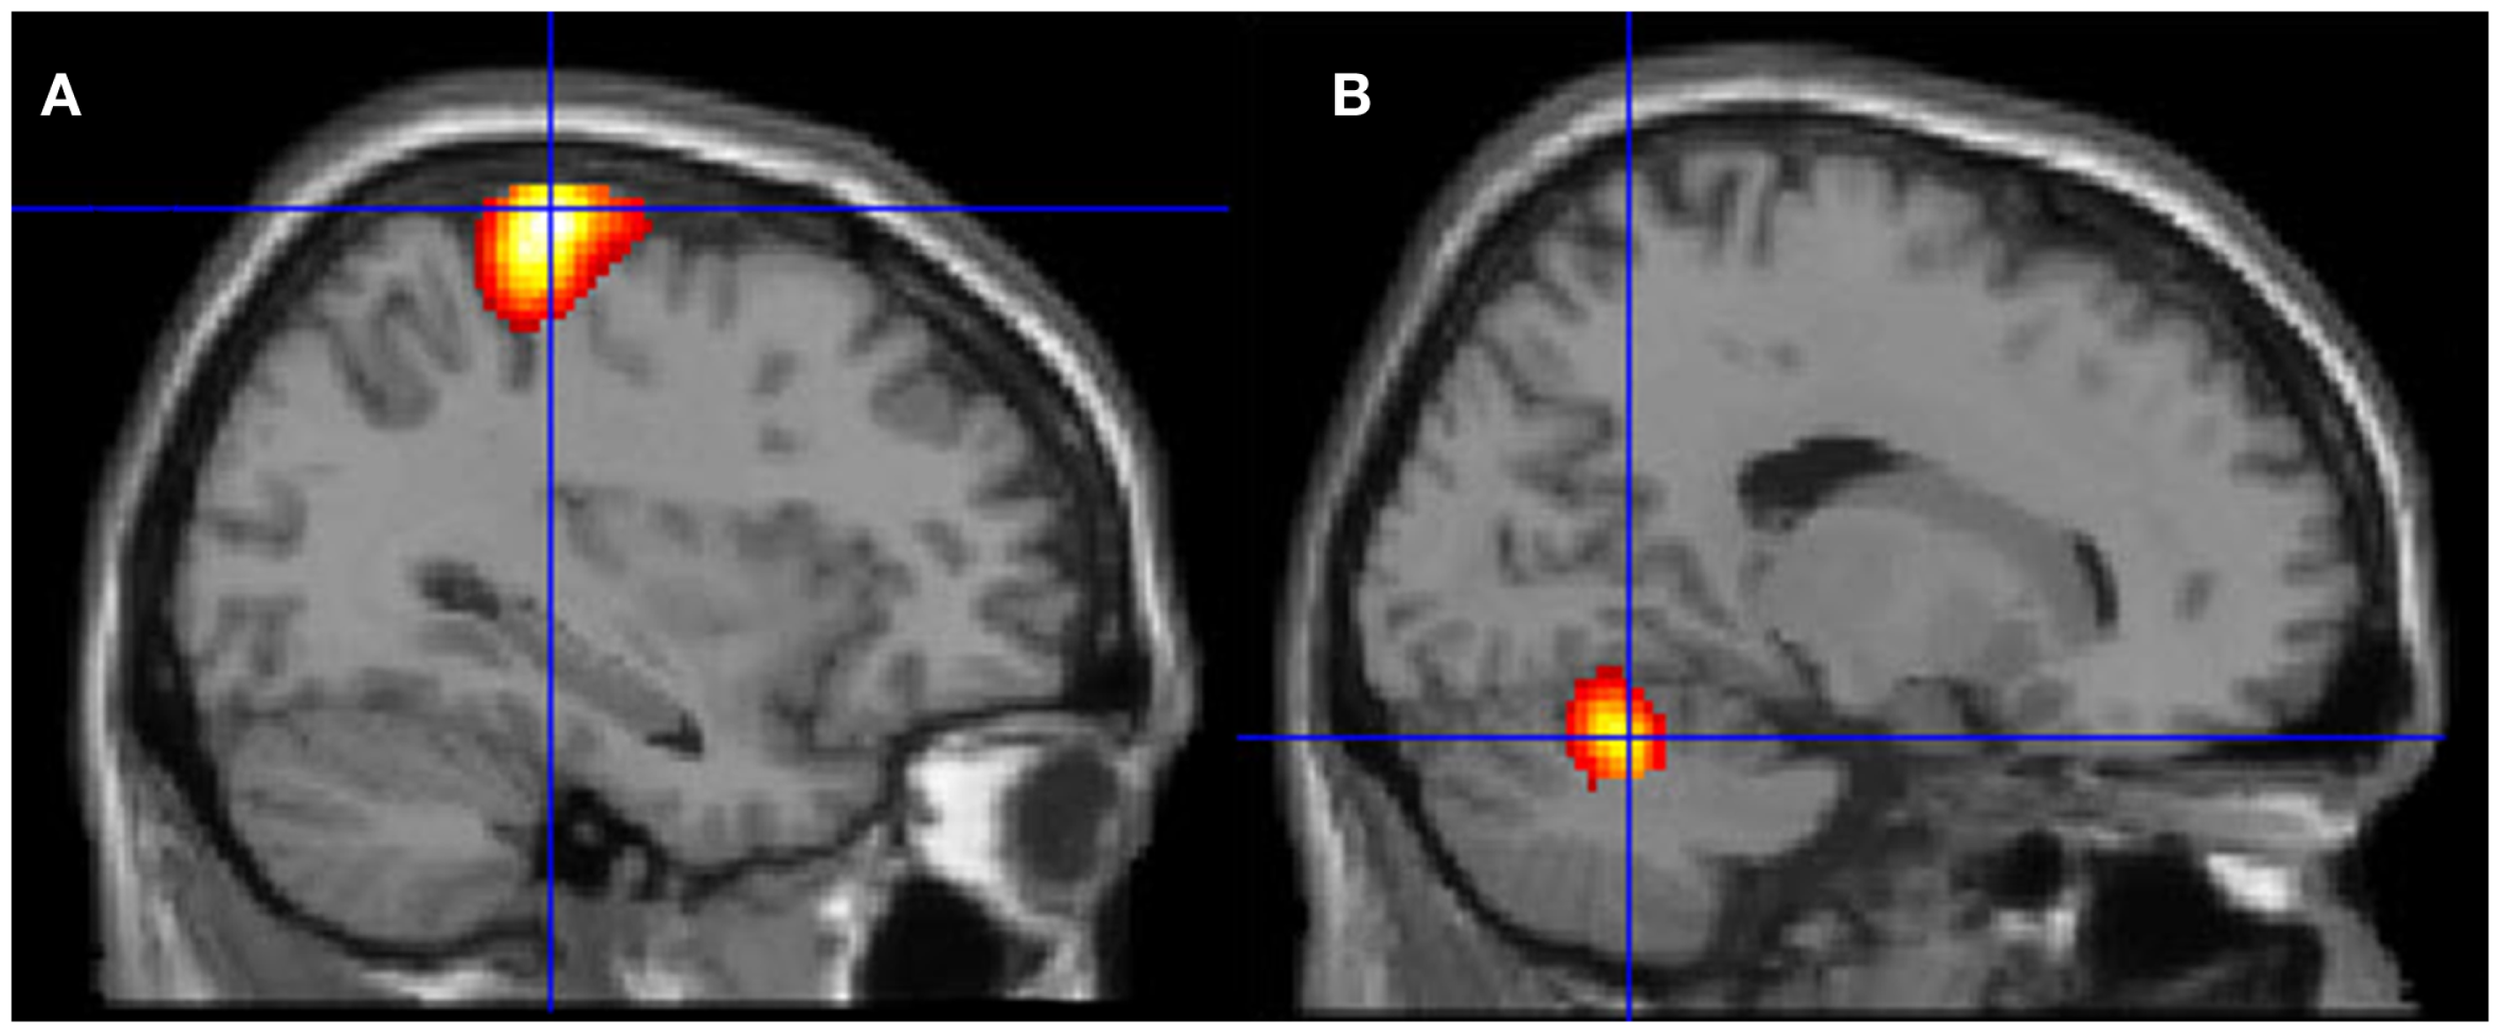

Neural activation patterns for each of these ECE Runs were analyzed separately with rest subtracted from the experience. Given the lack of significant difference between the results of each of the three Runs, all ECE Runs were combined into one analysis to increase power and observe brain regions that were concomitantly activated for each Run. Results are reported with a family wise error (FWE) very stringent correction for multiple comparisons at 0.001. Results are presented in Figure 1. The most significantly and consistently activated areas during the ECE compared to the non-ECE blocks were left lateralized in the supplementary motor area (SMA) (x, y, z = −2, −18, 62, cluster 247, T = 6.66, p = 0.001), supramarginal gyrus/posterior superior temporal gyrus (x, y, z = −64, −46, 24, cluster 60, T = 6.04, p = 0.001), inferior temporal gyrus (x, y, z = −48, −54, −20, cluster 72, T = 5.89, p = 0.001), middle and superior orbital frontal gyri (x, y, z, = −26, 56, −10, T = 5.05, p = 0.001), and the cerebellum (x, y, z = −50, −48, −30, T = 5.76, p = 0.001). The parietal and superior temporal activation taken together correspond to the temporal parietal junction. There was significantly less activation during the ECE blocks compared to non-ECE blocks (Figure 2) in bilateral posterior visual regions: the lingual gyrus (x, y, z = 14, −64, 4, cluster 19205, T = 13.23, p = 0.001) and the cuneus (x, y, z = 0, −92, 18, cluster 19205, T = 12.71, p = 0.001).

Figure 1. Rendered image of significantly activated regions of the brain while the participant was having extra-corporeal experiences. Most significantly activated regions are lateralized to the left side and include the supplementary motor area (F), the cerebellum (B,D,E), the supramarginal gyrus (D,F), the inferior temporal gyrus (B,D,F), the middle and superior orbitofrontal gyri (A,C,D,E). The p-value was set at 0.001 uncorrected for this image with the cluster threshold at 200 significant voxels.

The ECE was reported as a mixture of visual imagery and kinesthetic imagery but the kinesthetic component was prominent as evidenced by the report of feeling dizzy when performing a rotational movement. The prominence of kinesthetic experience over the visual experience is consistent with a strong bilateral deactivation of the lingual gyrus and cuneus encompassing the primary visual cortex. Activations are mainly left-sided and involve the left SMA, supramarginal and posterior superior temporal gyri (the last two overlap with the temporal parietal junction, which has been associated with out-of-body experiences). The cerebellum also shows strong activation that is consistent with the participant’s report of the impression of movement during the ECE. There are also left middle and superior orbital frontal gyri activations, structures often associated with action monitoring.

The TPJ activation that was observed during the ECE is consistent with patient cases that report autoscopy and out-of-body experiences when the functional integrity of that area is altered (Blanke et al., 2004; Blanke and Mohr, 2005; Blanke, 2012). Studies of experimentally induced altered body imagery have demonstrated that transcranial magnetic stimulation of the TPJ area can interfere with the ability of healthy individuals to imagine themselves in body orientations similar to out-of-body experiences (Blanke et al., 2005). Electrical stimulation of the TPJ in epileptic patients also produces various sensations associated with out-of-body experience (Blanke et al., 2002). Interestingly, several of the active clusters found in the present experiment during the ECE (left supramarginal gyrus, left inferior temporal gyrus, left cerebellum) correspond closely to clusters with mirror properties associated with action observation and execution that were identified by a recent meta-analysis (Molenberghs et al., 2012).